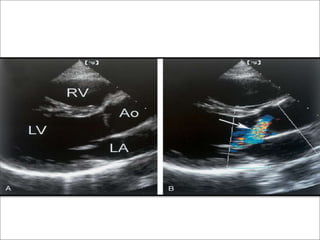

Two dimensional imaging

• 1.Abnormal mitral valve motion due to impingement on the

anterior leaflet by a posteriorly directed aortic regurgitation jet –

deformation of leaflet during diastole.

• 2.Dilation of the sinotubular junction – loss of the geometry of

aortic leaflet coaptation – jet arises centrally.

• 3.Causes of acute AR – IE can be identified.

• 4.Paravalvular abscess leading to acute AR.

• 5.Aortic dissection causing AR can be detected.

• 6.LV response to volume overload - dilation of LV –spherical

shape.

• 7.LV mass increases.

• 8.Hyperdynamic IVS motion.

Jet area

• In PSax view

• Using color doppler

• Compared to LVOT area

1+ 0-3%

2+ 4-24%

3+ 25-59%

4+ >60%